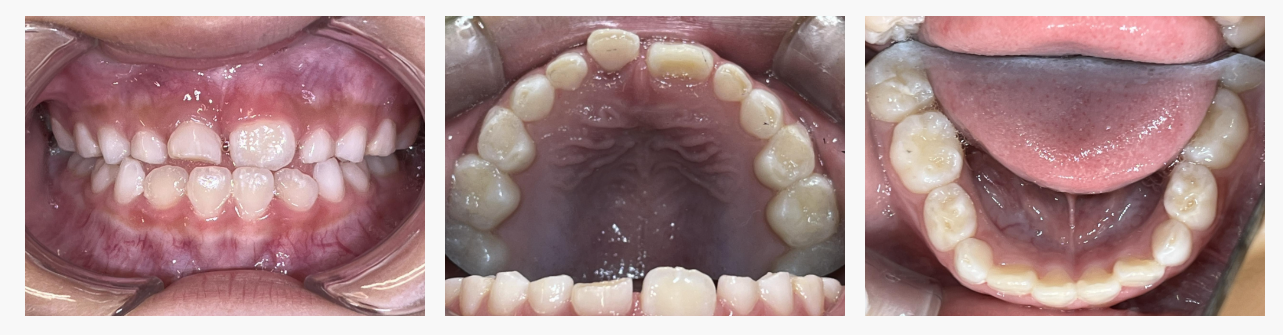

▼ After(治療後)

24ヶ月で、自然な噛み合わせとバランスの良い口元へ改善しました。

■ 治療結果

・反対咬合が改善し、自然な噛み合わせに

上あごの成長が進み、横幅・前後バランスが整った

・呼吸が安定し、口がポカンと開く癖が減少

・発音が明瞭になりやすい環境に改善